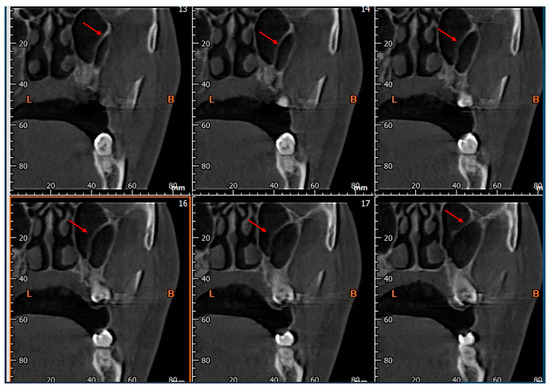

- The presence of the septa on cross-section (Figure 4);

- The height of the septa on cross-section setting from 2 mm to 0 mm, to better evaluate the maxillary sinus: this was measured from the apex of the septa to its bottom on the basal bone;